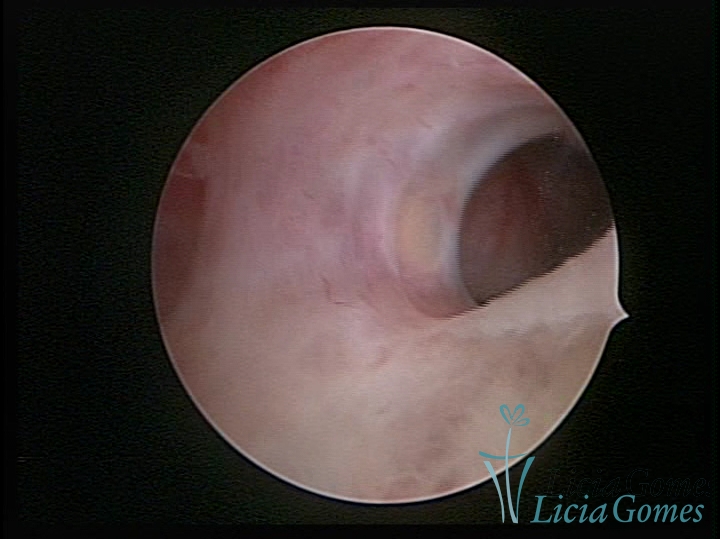

• SINÉQUIA TIPO FIBROSA